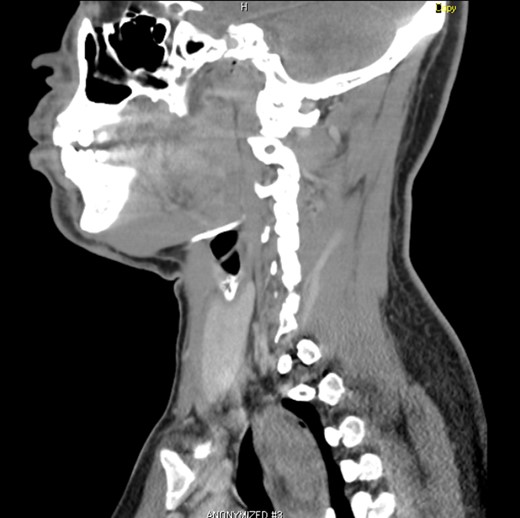

A 37-year-old male coughed up a large mass into the back of his mouth while swallowing. He pushed the mass back down his throat and he sought medical attention following this episode. He has chronic depression and smoked a pack of cigarettes a week for thirteen years but stopped smoking a year prior to presentation. A barium swallow was done which was reported as either an ‘… oesophageal duplication cyst of the cervical oesophagus … or less likely a polyp.’ A CT scan confirmed an intraluminal cervicothoracic oesophageal lesion consistent with a large fibrovascular polyp. He then underwent upper gastrointestinal endoscopy which confirmed a large mass on a stalk extending from the cervical oesophagus to 30 cm into the oesophagus. He was then referred for surgical resection. Clinical examination identified a Grade II/VI systolic murmur. Echocardiogram showed mild tricuspid, mitral and pulmonary regurgitation with mitral valve prolapse and a small secundum atrial septal defect. A preoperative diagnosis of a giant fibrovascular polyp (GFP) of the oesophagus was made, and the patient was scheduled for surgical excision.